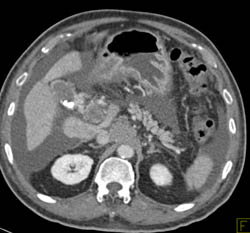

Hepatoma and Incidental Gastric Cancer